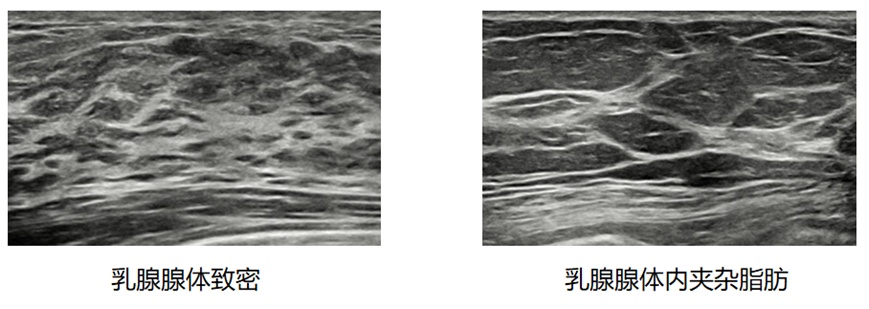

每个人的乳腺结构是不同的,有些人的腺体比较致密,有些人的腺体里夹杂的脂肪较多,都会影响触诊的结果。

下面,我们通过两张图像让大家直观的感受一下两种乳腺底板的区别。